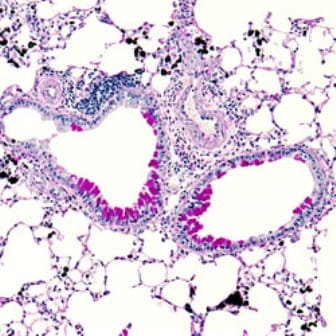

Asthma is a chronic disease that impacts millions of children worldwide. Other atopic diseases, such as eczema and food allergies, can also predispose children to asthma development. Within the affected population, asthma can have a variety of symptoms, making treatments challenging.

Our research is dedicated to uncovering the biological, environmental and genetic links that drive asthma development and progression. Our main research goals are to understand why its severity varies among children and how other allergic diseases contribute to asthma development. By focusing on early biomarkers, immune and inflammatory responses in allergic diseases, and changes in airway reactivity, our team focuses on predicting the severity of the disease for each patient and understanding mechanisms that drive asthma progression. Ultimately, our research aims to prevent asthma exacerbations and reduce hospitalizations leading to improved daily life for patients.